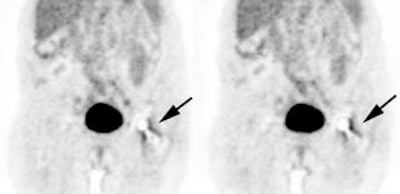

Normal uterine activity: Faint uterine uptake is common (black arrows). |

Normal testicular activity: Mild symmetric testicular uptake can be seen (black arrows). |